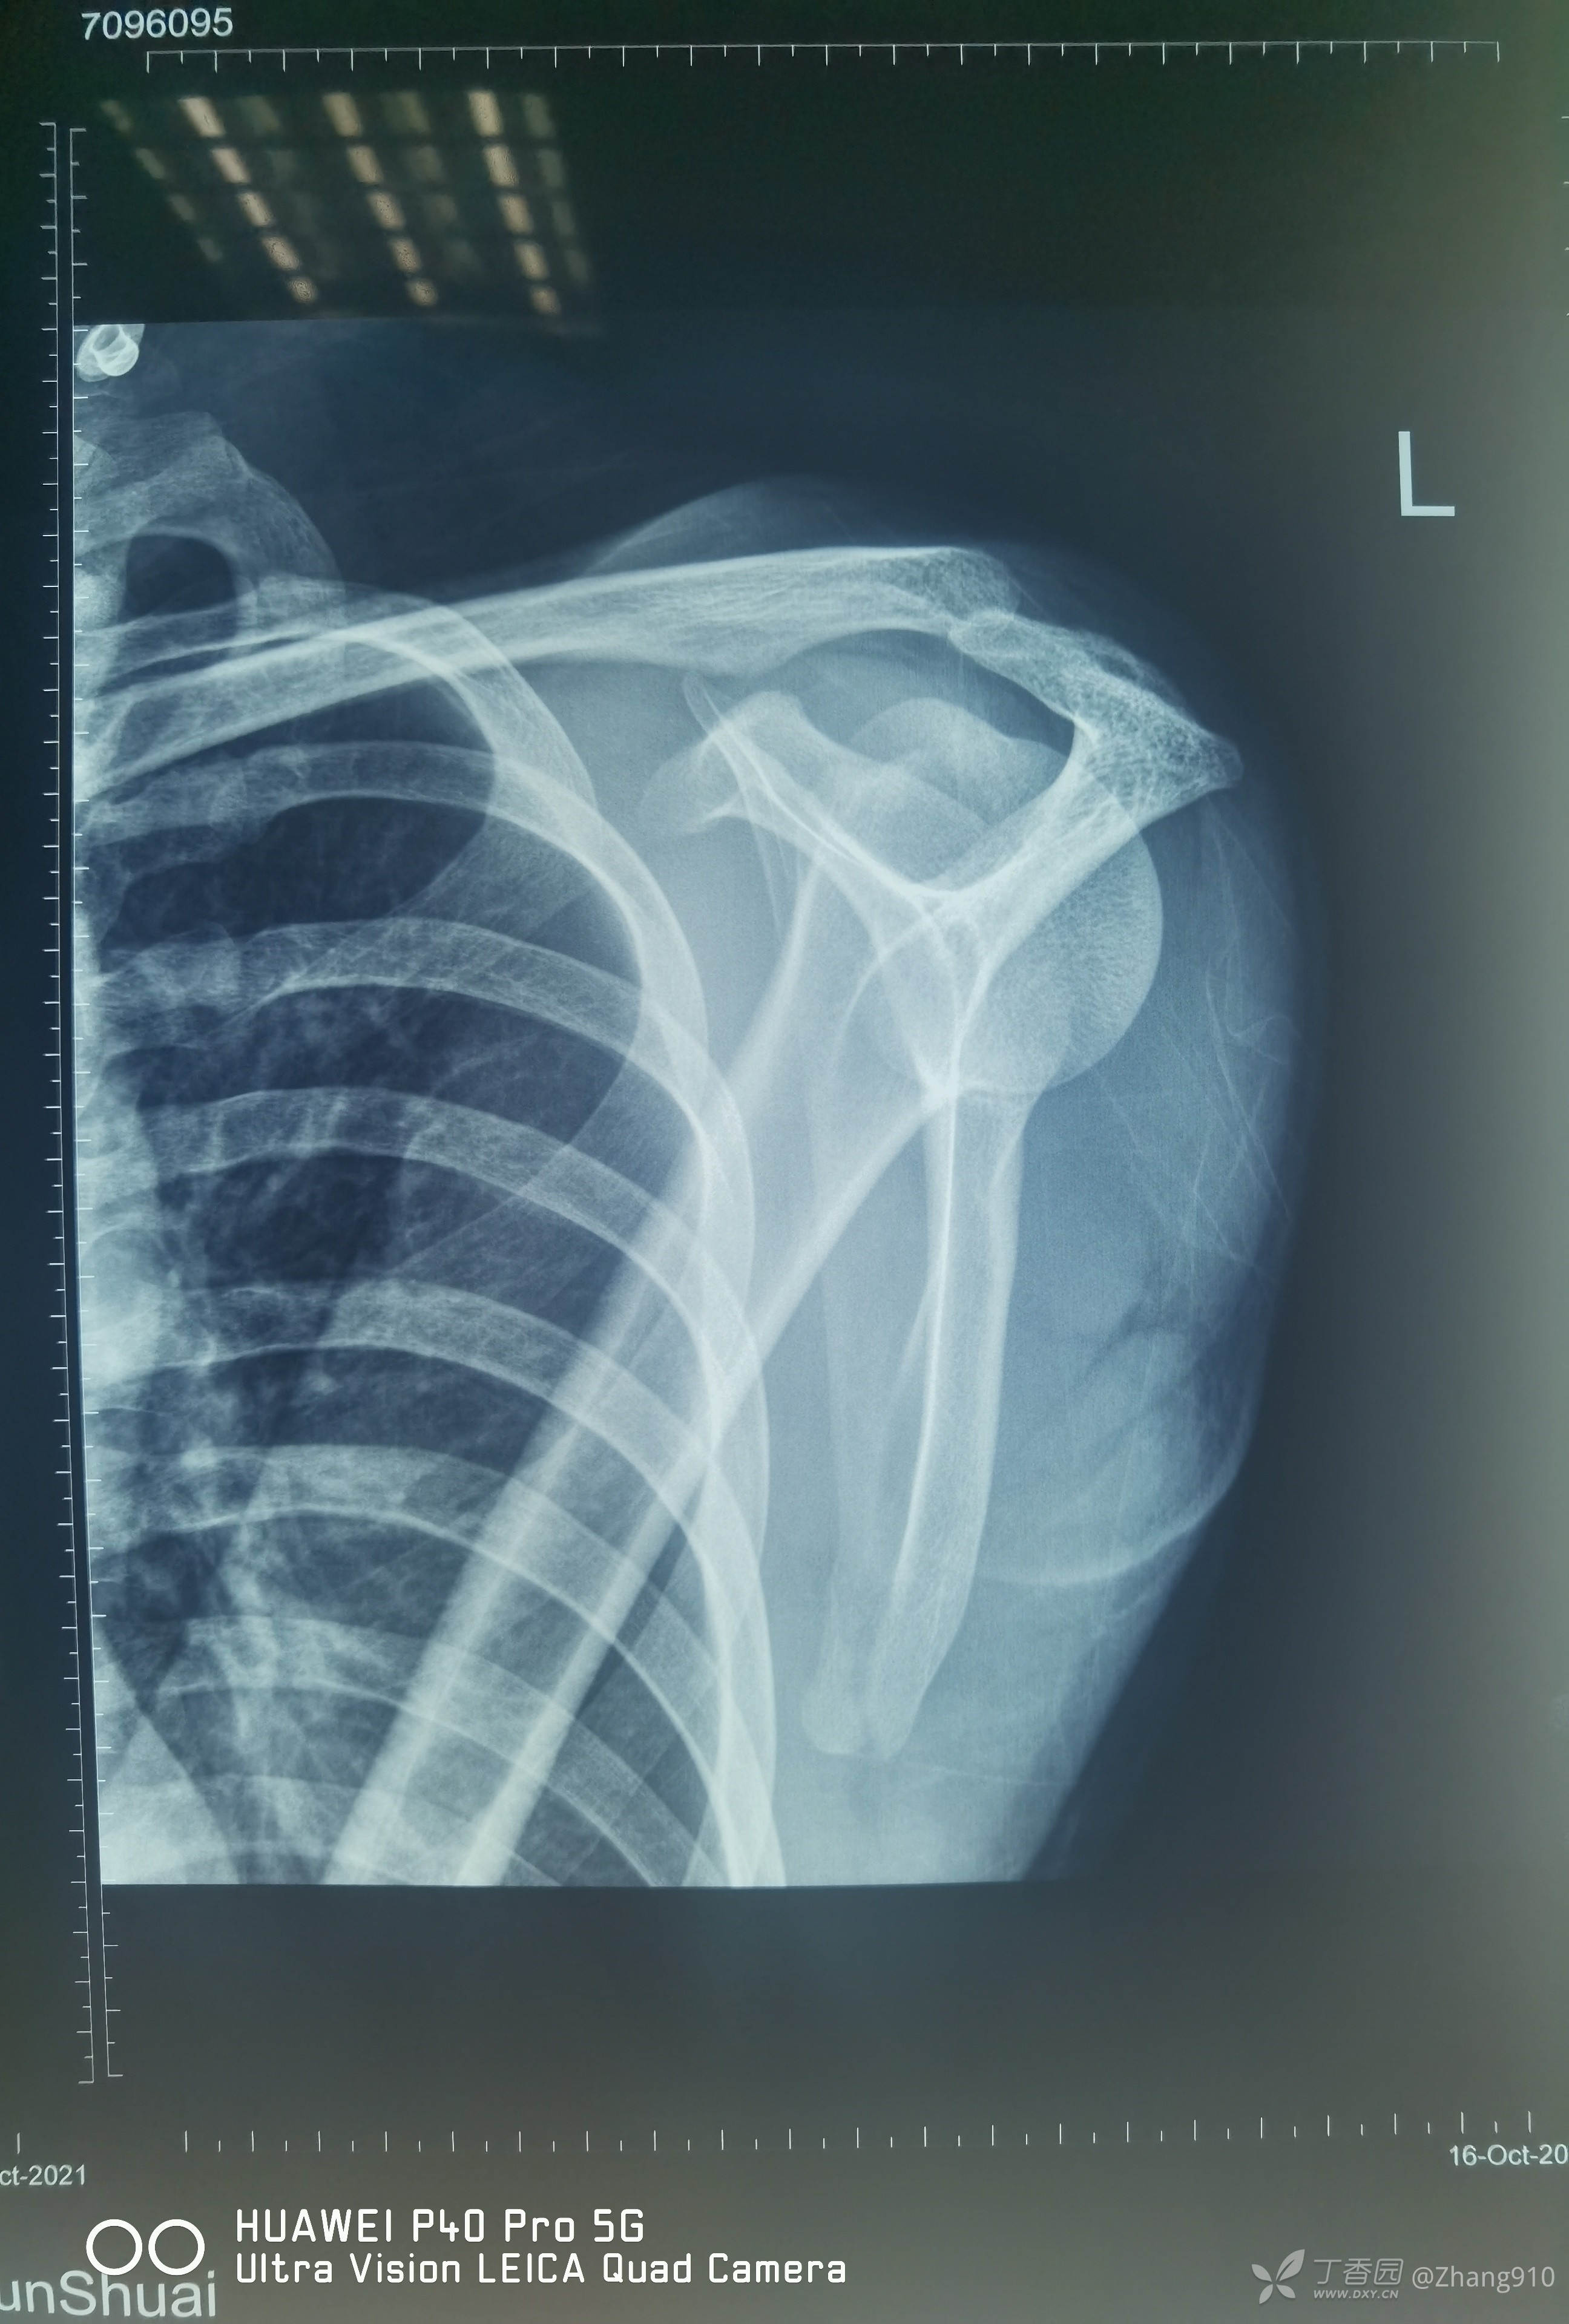

辅助检查:

X线显示:第3、5掌骨骨折

肩关节查体没有明显异常

肩关节核磁共振: